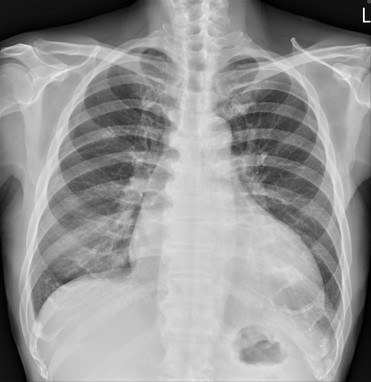

Chest X ray showed cardiomegaly. ECG showed atrial fibrillation rhythm with poor R progression. Echocardiography revealed markedly depressed left ventricular systolic function, with a left ventricular ejection fraction (LVEF) of 20.19%, accompanied by moderate mitral and tricuspid regurgitation.